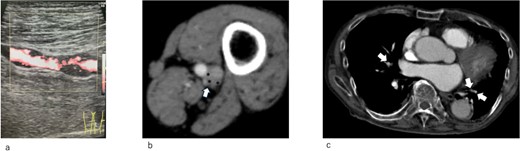

A 93-year-old man was admitted to our emergency clinic with a left femoral fracture. He presented with severe hypoxemia and shock. Treatment included high-density oxygen administration using noninvasive positive pressure ventilation (NPPV), fluid resuscitation, and epinephrine administration. Duplex ultrasonography revealed deep venous thrombosis (Fig. 1a). Computed tomography of the enhanced pulmonary artery and lower extremity veins revealed pulmonary thromboembolism and deep venous thrombosis in the left superficial femoral and popliteal veins (Fig. 1b and c). Echocardiography revealed right ventricular dilation and pulmonary hypertension at 43 mmHg. D-dimer and NT-proBNP levels significantly increased to 48 and 1941 pg/ml, respectively. Immediate heparin administration was contraindicated because the patient was at risk of hemorrhage from the femoral fracture. IVCF implantation was recommended.

(a) Duplex ultrasonography image of the left superficial vein on admission. A thrombus is observed in the vein. (b) Enhanced computed tomography on admission. Left popliteal venous aneurysm (arrow). A thrombus is observed in the aneurysm (*). (c) Enhanced computed tomography on admission. A pulmonary embolism is observed (arrow)